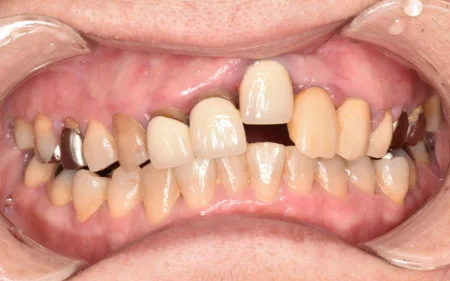

一般歯科 2023.0450代男性「着色を落として、詰め物もやり直したい」歯周病治療と専用機械による着色除去を並行し、歯と歯肉の状態を改善して詰め物をやり直す準備ができた症例